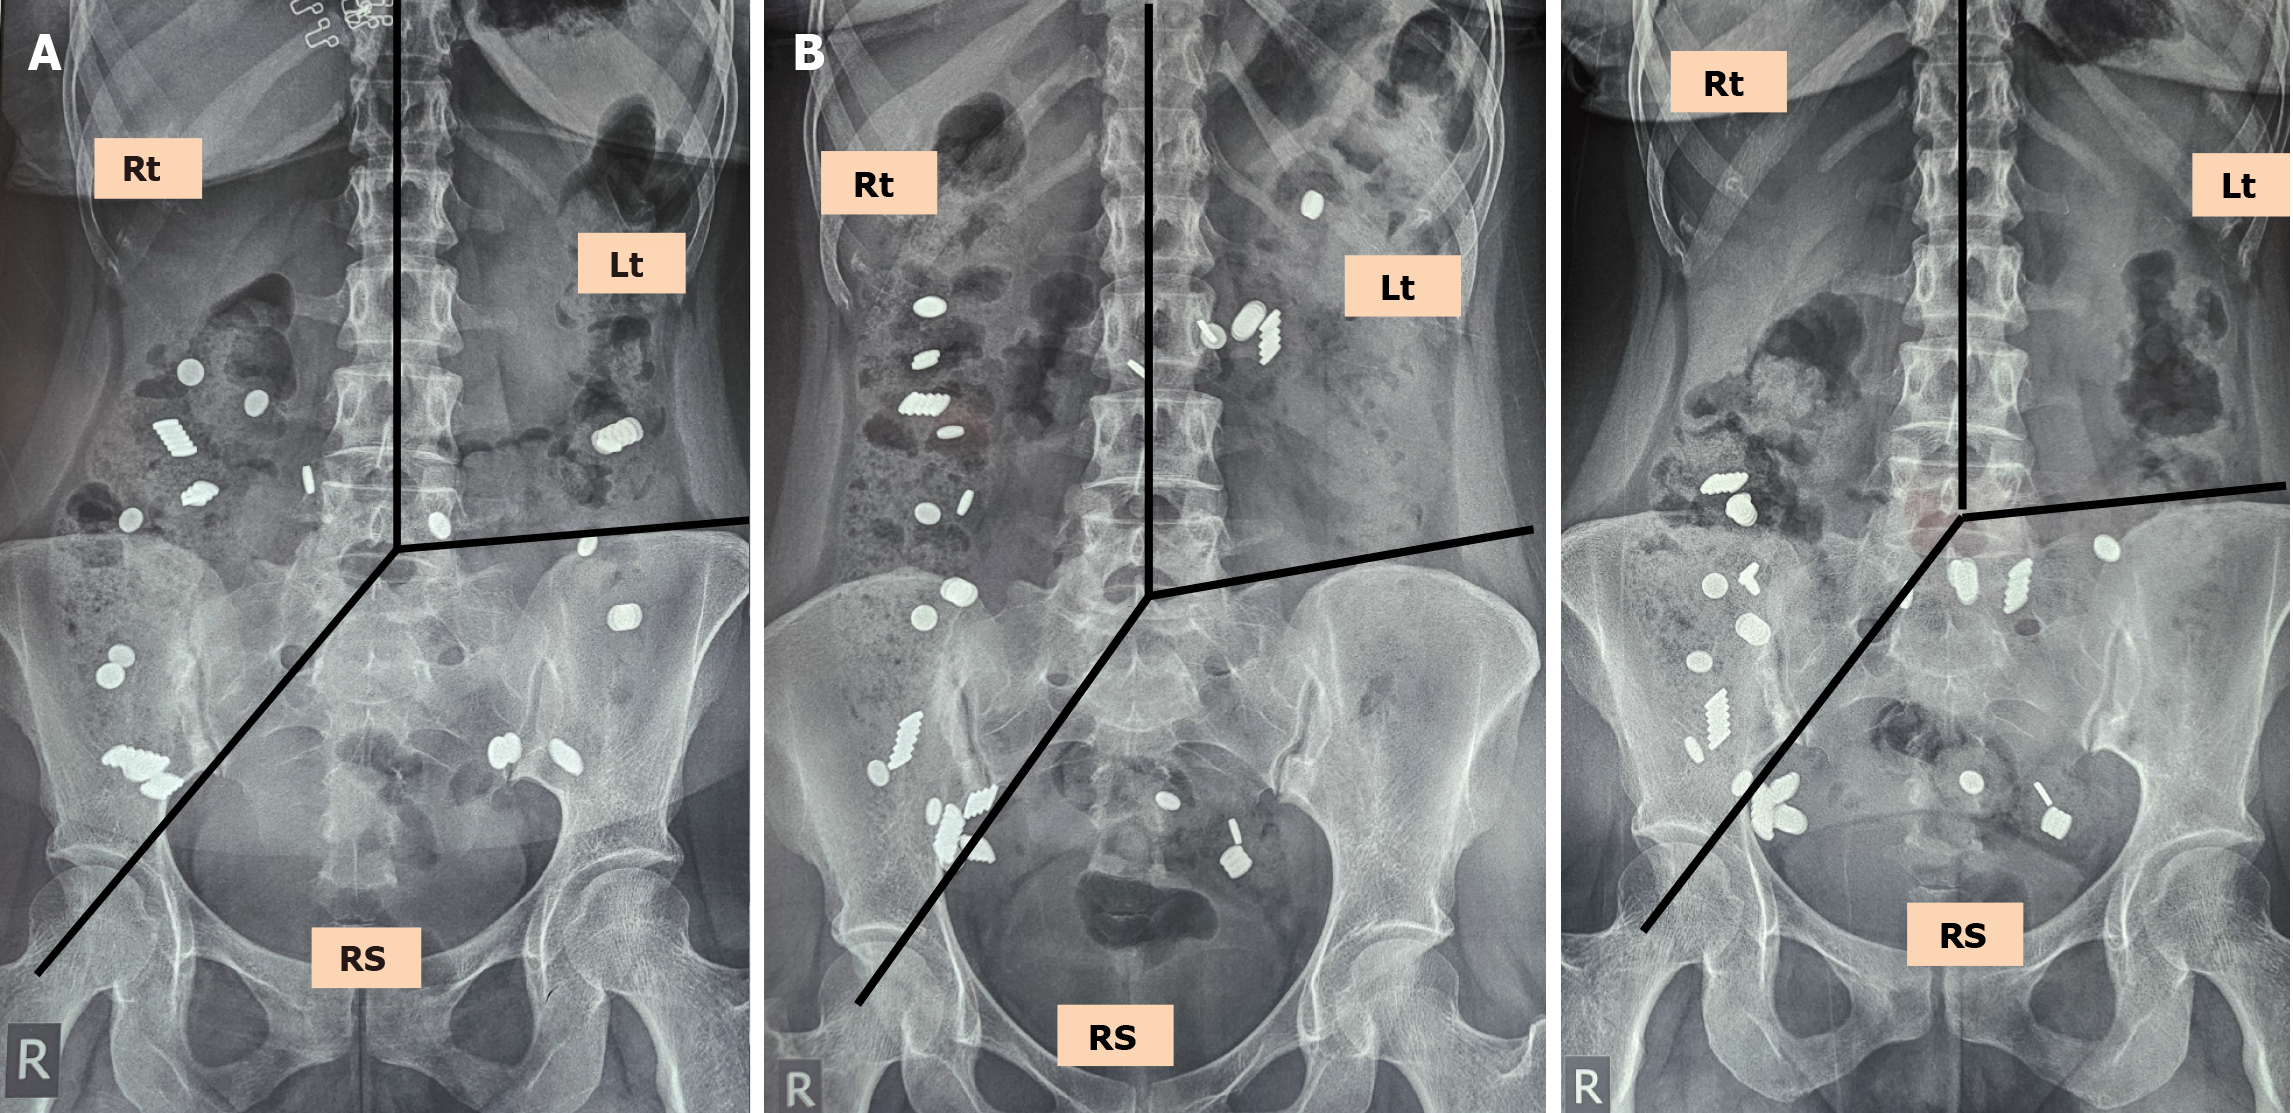

However, these Western protocols often fail to capture meaningful ROM retention in Asian populations due to their characteristically rapid transit times. As a result, Indian researchers have adapted protocols to better suit local physiology. For instance, Ghoshal et al[40] administered 20 ROM at 0 hour, 12 hours, and 24 hours with radiographs at 36 hours and 60 hours, finding that retention of ≥ 30 markers at 36 hours and ≥ 14 markers at 60 hours provided high sensitivity and specificity for detecting STC or DD. These adaptations highlight the necessity of tailoring protocols to the population under study, considering differences in diet, bowel habits, and baseline transit times (Figure 2A).

Figure 2

Figure 2 The X-ray. A: Plain abdominal radiograph for colonic transit time assessment using radiopaque markers. Three lines need to be drawn to divide the colon into three segments: A vertical line up to the middle of the body of the fifth lumbar vertebra, a line from the body of the fifth lumbar vertebra to the right pelvic outlet, and a line from the fifth lumbar vertebra to the anterior superior iliac crest on the left. These lines divide the colon into three segments: The right colon, left colon, and rectosigmoid (RS) colon. This distribution helps localize segmental delays in colonic transit and differentiates between normal transit, slow transit constipation, and RS outlet dysfunction; B: Comparison of supine (left) and erect (right) abdominal radiographs in a patient undergoing colonic transit time evaluation using radiopaque markers. Although the erect X-ray suggested accumulation of markers in the RS region, the supine film revealed that many markers presumed to be in the RS have shifted from the transverse colon and should be reassigned to the right and left colon. This discrepancy illustrates how gravity-dependent descent of the transverse colon in the erect position can lead to misclassification of marker location and result in a false diagnosis of pelvic floor dysfunction. In this case correct interpretation supports a diagnosis of slow transit constipation. Additionally, accumulation of markers in the cecal region may be erroneously attributed to the RS segment, further emphasizing the importance of anatomical correlation in marker assignment. Rt: Right; Lt: Left; RS: Rectosigmoid.

Imaging technique selection is an essential determinant of ROM CTT study assessment. Despite the widespread use of abdominal radiography as the standard imaging modality in these studies, there remains a lack of consensus regarding the number and type (supine or erect) of abdominal radiographs to be performed at a particular time frame. This methodological variability introduces potential discrepancies in the interpretation of marker distribution, which can directly impact the diagnostic conclusion. When abdominal radiographs are obtained in the erect position, the gravitational influence on the transverse colon may lead to its downward displacement into the pelvic region[41-43]. This anatomical shift can result in the erroneous localization of ROMs, creating a false impression of marker retention in the rectosigmoid region and consequently leading to an incorrect diagnosis of functional outlet obstruction (Figure 2B). To mitigate these limitations, a single abdominal radiograph taken in the supine position is preferable because it results in a lower radiation dose and better interpretation compared with the erect position radiograph[1,15,26,44].